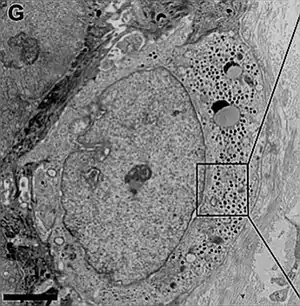

- Microscopía electrónica

En la ultraestructura el citoplasma aparece claro, pero contiene gránulos de centro oscuro (electrón-densos) pequeños de 80-120 nm y esféricos. También muestra filamentos oscuros, cortos y paralelos. El retículo endoplásmatico es grande al igual que el Golgi, lo que demuestra síntesis y secreción.

El núcleo es lobulado con indentaciones profundas y paralelo a la superficie del epitelio.

La cromatina se muestra poco condensada, lo que implica tasas de transcripción elevada. Se ven uno o dos nucléolos.

El citoplasma emite prolongaciones con forma de dedo o espiga hacia la epidermis, que se interdigitan con los queratinocitos circundantes mediante desmosomas.[9] Aquí son numerosos las uniones estrechas tipo desmosomas.

En el sector basal, las células de Merkel presentan una especialización, de forma discoidal que contacta directamente con dendritas pertenecientes a neuronas aferentes.[11][3]